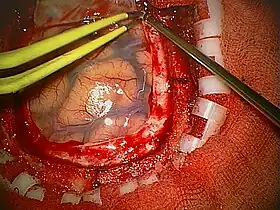

A craniotomy is a surgical operation in which a bone flap is temporarily removed from the skull to access the brain. Craniotomies are often critical operations, performed on patients who are suffering from brain lesions, such as tumors, blood clots, removal of foreign bodies such as bullets, or traumatic brain injury (TBI), and can also allow doctors to surgically implant devices, such as deep brain stimulators for the treatment of Parkinson's disease, epilepsy, and cerebellar tremor. The procedure is also used in epilepsy surgery to remove the parts of the brain that are causing epilepsy.

Diagram of the elements of a craniotomy.

Human craniotomy is usually performed under general anesthesia but can be also done with the patient awake using a local anaesthetic; the procedure, typically, does not involve significant discomfort for the patient. In general, a craniotomy will be preceded by an MRI scan which provides an image of the brain that the surgeon uses to plan the precise location for bone removal and the appropriate angle of access to the relevant brain areas. The amount of skull that needs to be removed depends on the type of surgery being performed. The bone flap is mostly removed with the help of a cranial drill and a craniotome, then replaced using titanium plates and screws or another form of fixation (wire, suture, etc.) after completion of the surgical procedure. In the event the host bone does not accept its replacement, an artificial piece of skull, often made of PEEK, is substituted. (The PEEK appliance is routinely modeled by a CNC machine capable of accepting a high resolution MRI computer file in order to provide a very close fit, in an effort to minimize fitment issues, and therefore minimizing the duration of the cranial surgery.)